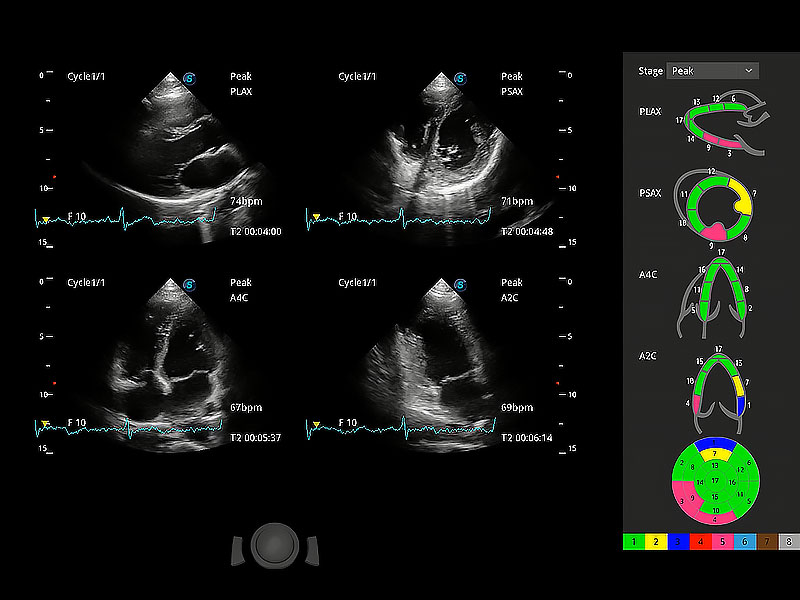

通过心肌识别技术与二维斑点追踪技术相结合,对心脏的超声图像进行量化分析。计算心肌17个节段的应变、应变率、速度、位移等,并通过牛眼图的形式进行呈现。

具备多种协议可选,同时支持17阶段划分法和专业的SE报告。